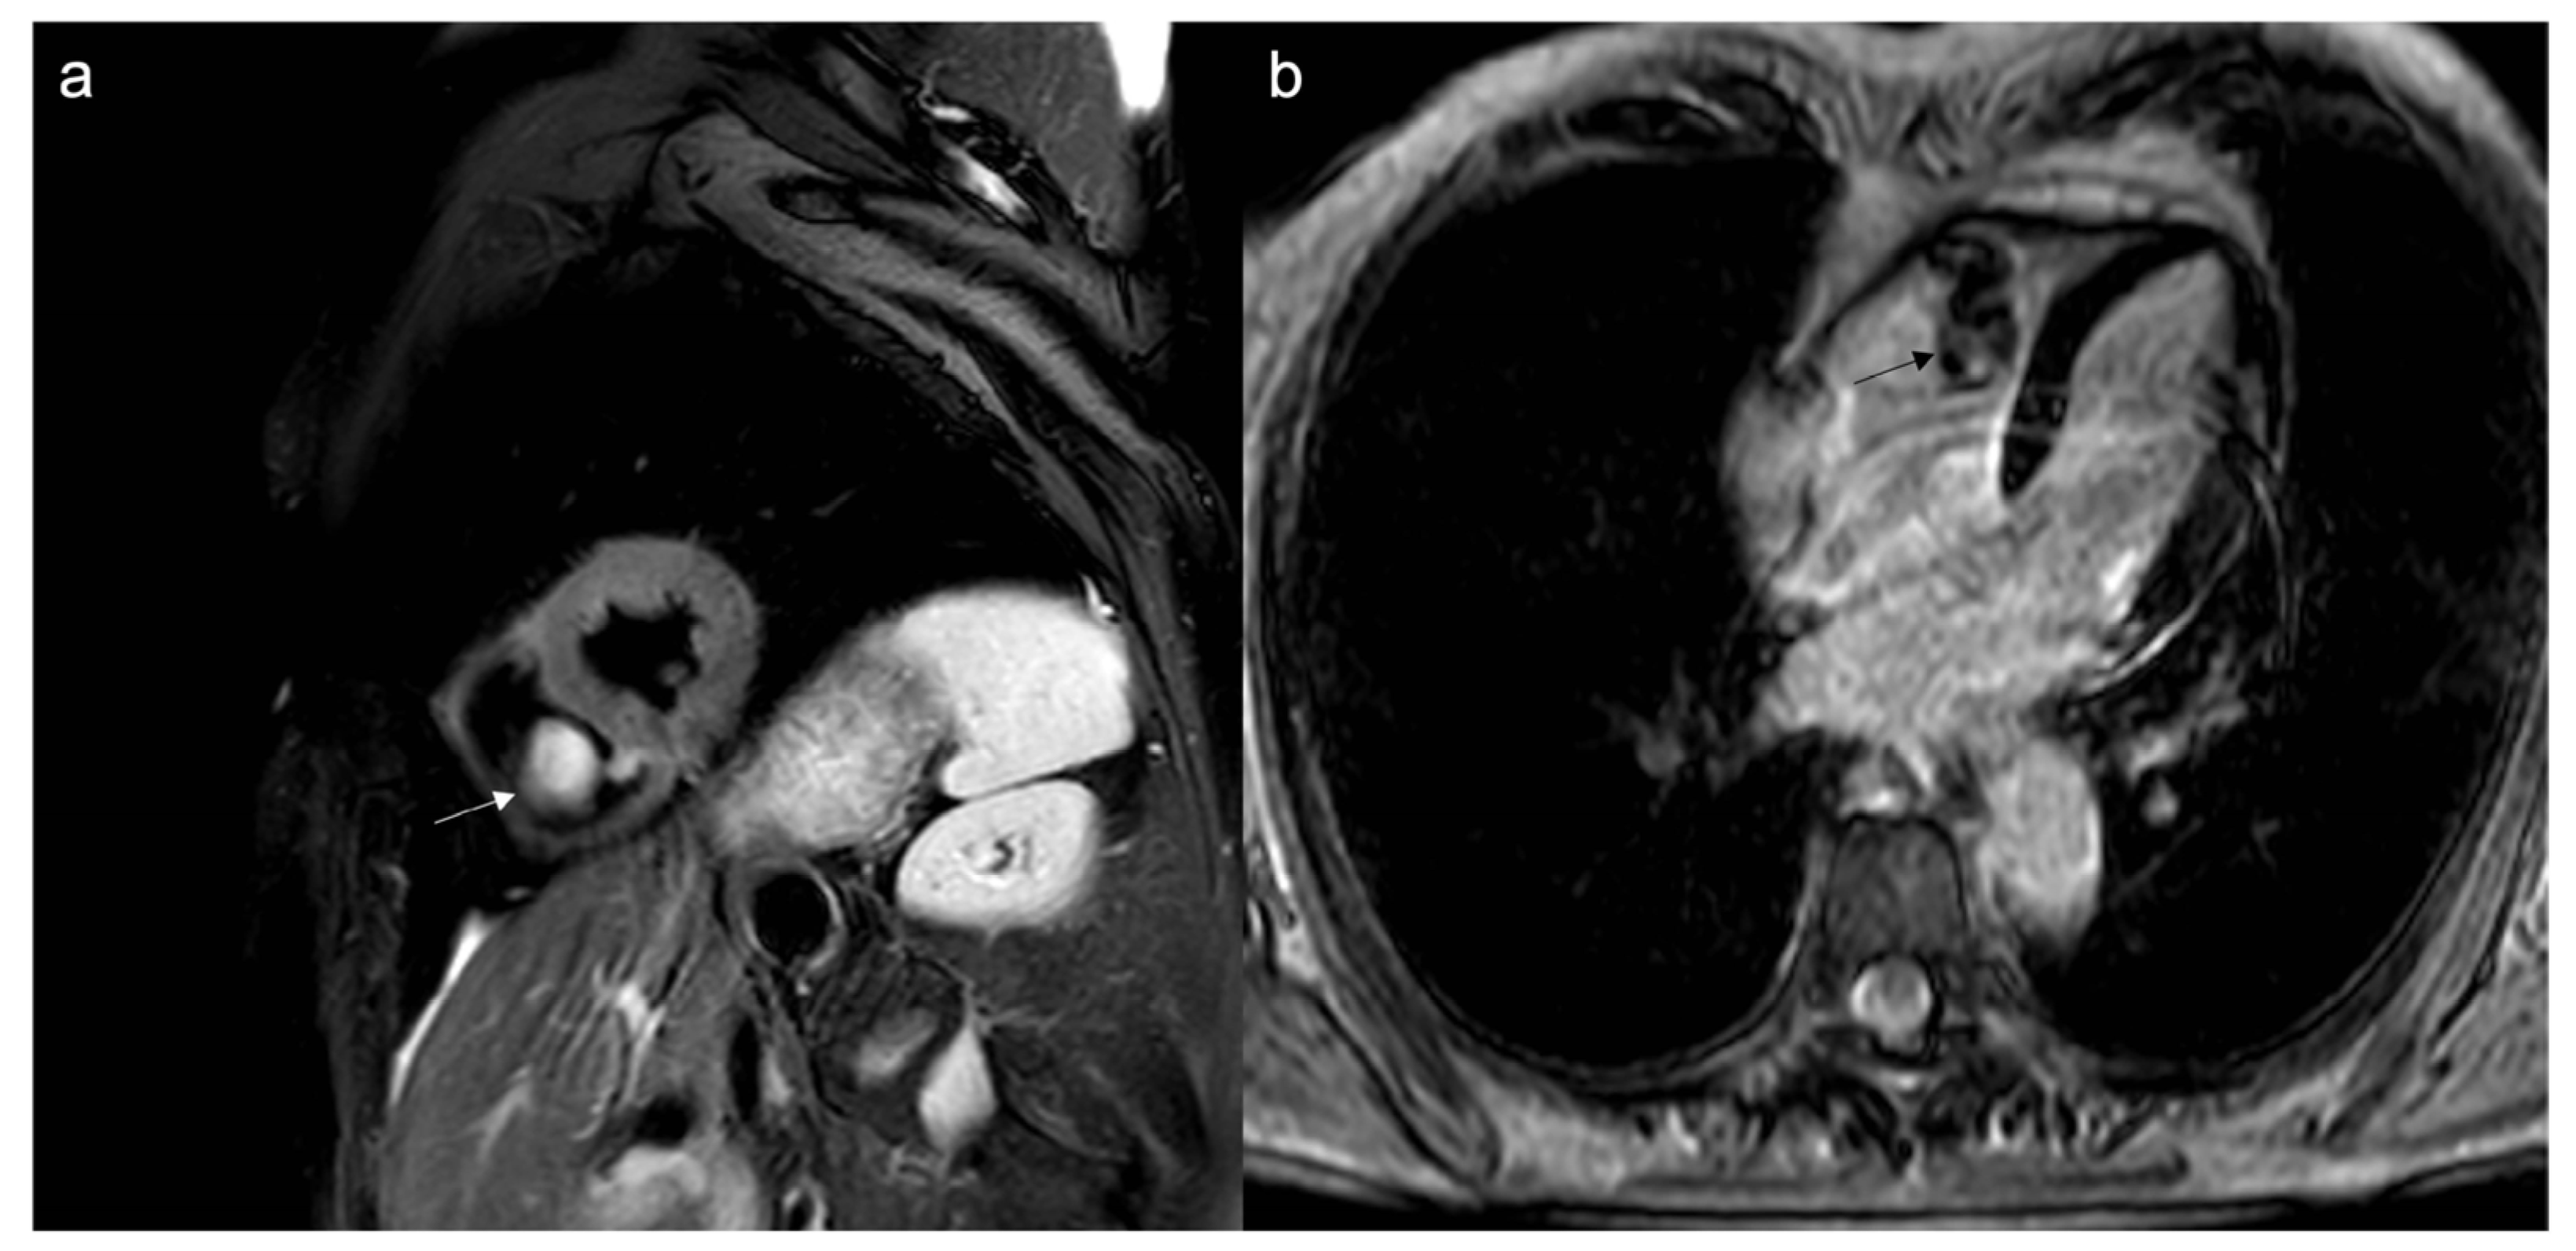

- ECV can be of help in differentiating hypertrophic cardiomyopathy (HCM) from other conditions that may mimic it (Figure 14 and Figure 15) [69].

Figure 14. Suspected HCM in a 14-year-old child, with asymmetric hypertrophy of the left ventricle. In T2w, the septal signal is very different from other myocardial segments (a), and it shows intramyocardial LGE (b), with a slight increase in T1 native values, approximately 1000 ms (normal value < 950 ms in our site) (c) and increased ECV around 41% (normal value < 30%) (d). The diagnosis was overturned and confirmed as a fibroma.

Figure 15. Another case of intramyocardial fibroma in a 5-year-old child, involving inferior-lateral and inferior-septal segments of the left ventricle, mimicking HCM; the mass shows an intense and homogenous LGE (a), with normal-low T1 native values (b), but a very high ECV, around 80%.